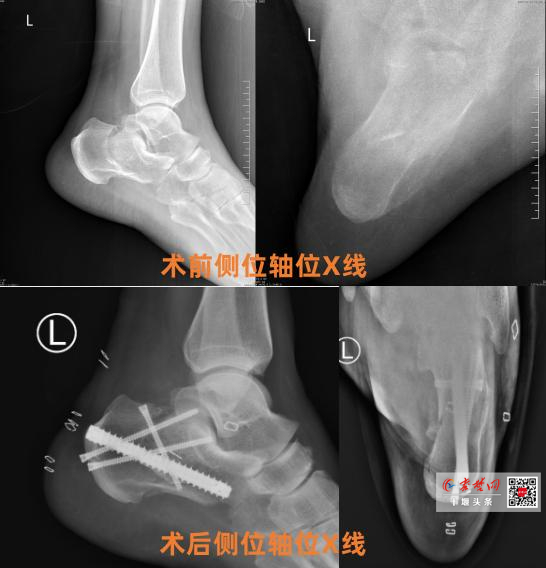

• 十堰人醫(yī)應(yīng)用“跟骨釘中釘”微創(chuàng)技術(shù)助骨折患者快速康復(fù)

十堰人醫(yī)應(yīng)用“跟骨釘中釘”微創(chuàng)技術(shù)助骨折患者快速康復(fù)

近日,十堰市人民醫(yī)院創(chuàng)傷骨科1病區(qū)成功完成一例采用“跟骨釘中釘內(nèi)固定系統(tǒng)”的微創(chuàng)手術(shù),為51歲左跟骨粉碎性骨折患者左先生實(shí)施精準(zhǔn)治療。術(shù)后患者恢復(fù)進(jìn)程顯著優(yōu)于傳統(tǒng)術(shù)式,次日即下地行走,充分凸顯了該技術(shù)的臨床優(yōu)勢(shì)?;颊咦笙取?/div>